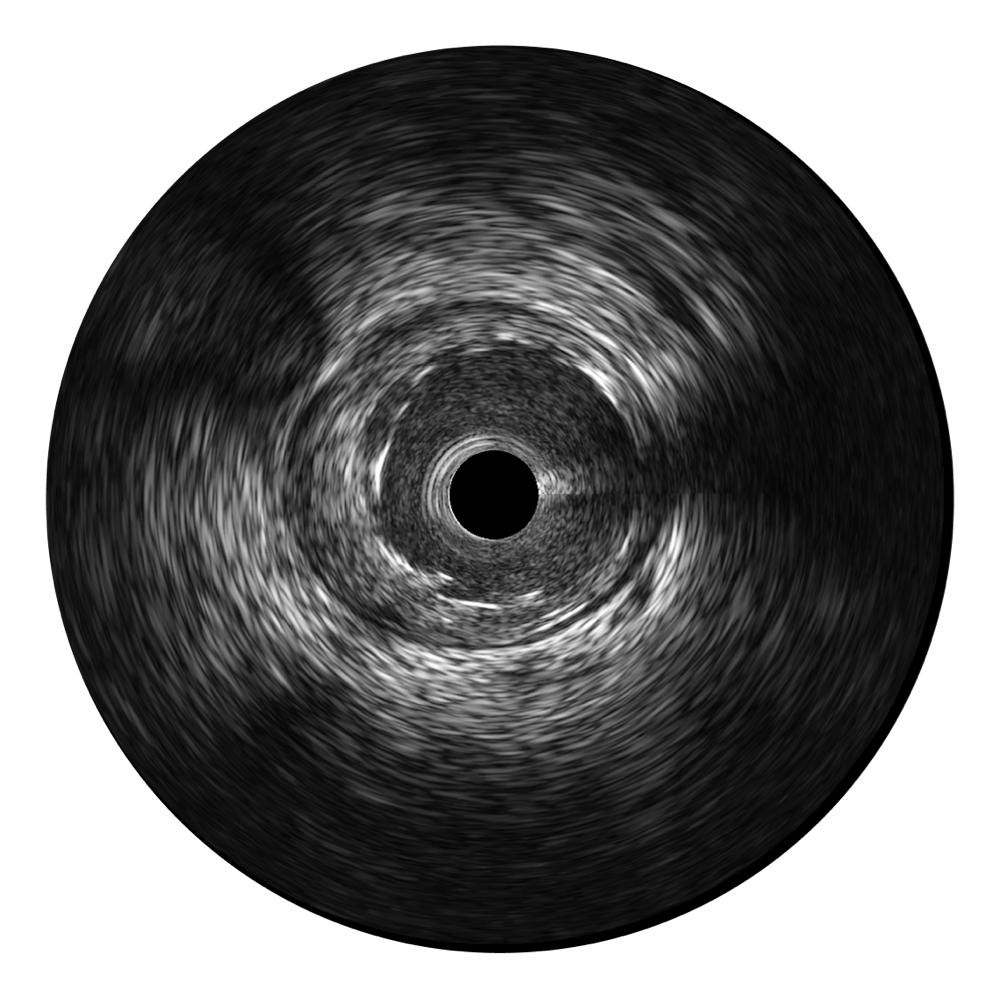

传统IVUS图像

对比传统IVUS导管成像,云顶集团官网宽频IVUS图像的近场支架梁显影更细腻,远场中膜外血管仍清晰可辨,兼顾远中近,兼顾分辨力与穿透深度